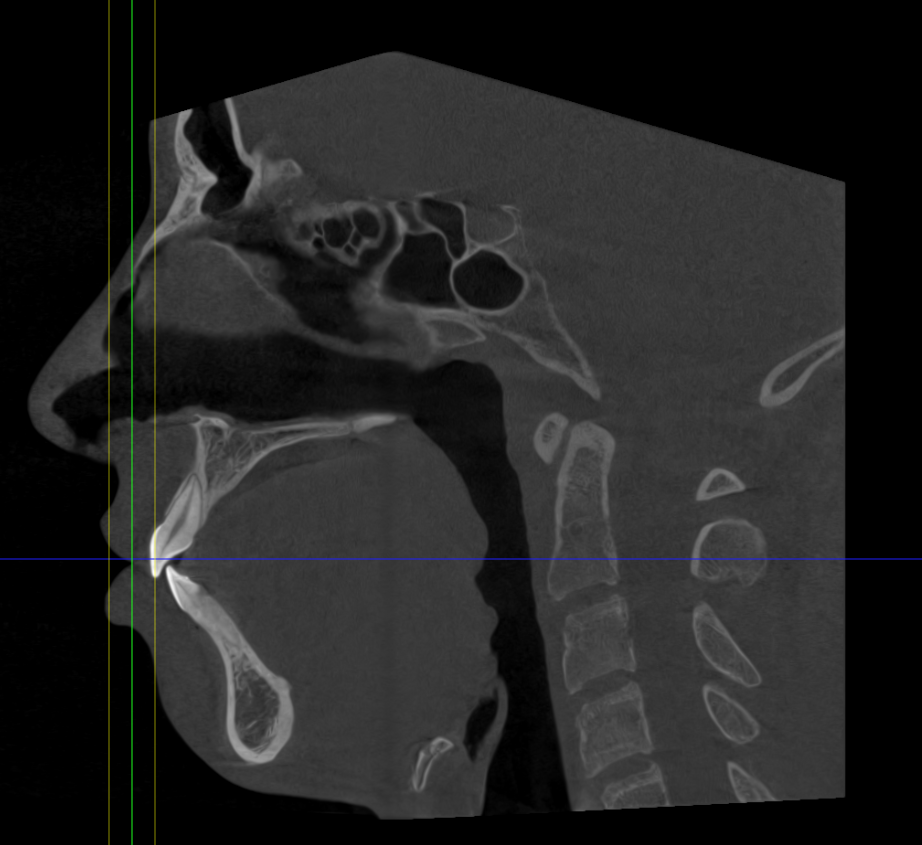

mandibular plane angle definitely not ideal

counter clockwise tri with segmental lefortwhat surg u getting bhai?